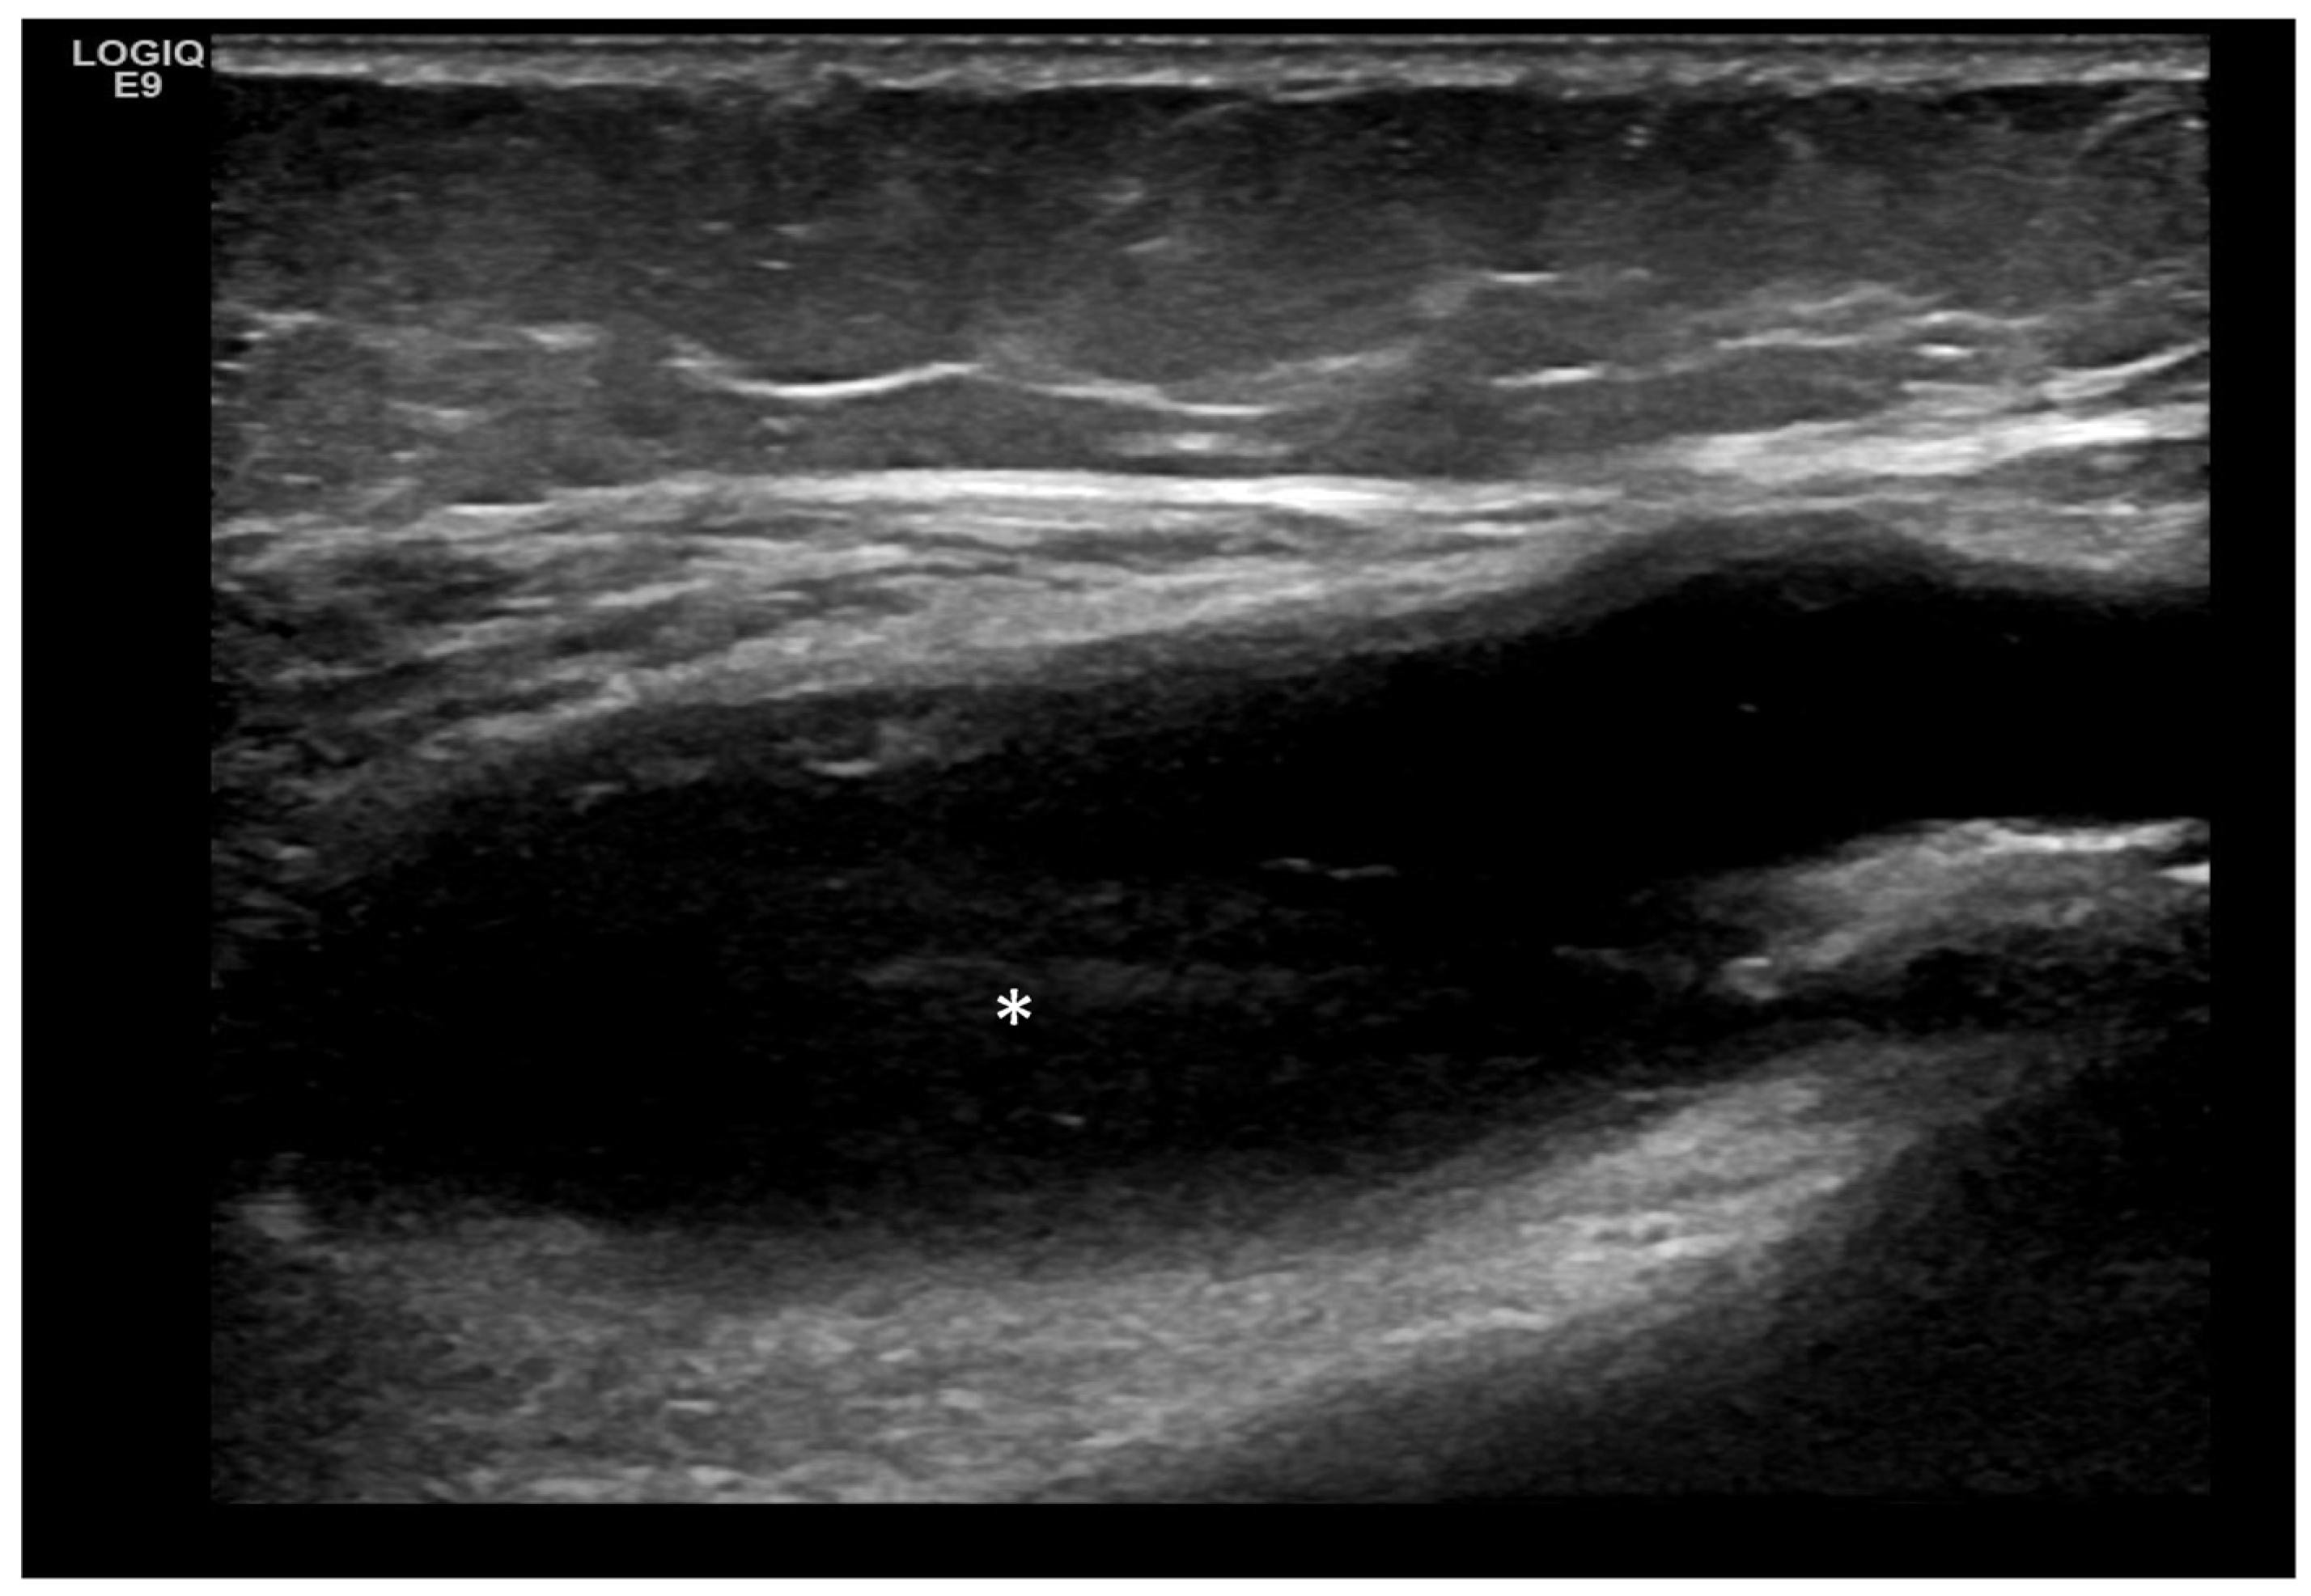

- Predominant intra-articular effusion (with minimal synovial proliferation (synovial sacs) and large intra-articular effusion;

4. Examples of US Phenotypes